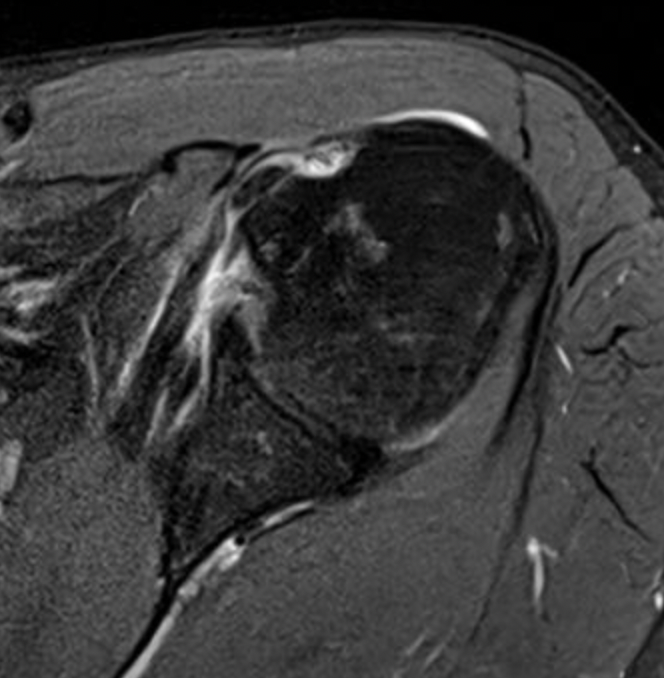

Medial subluxation with subscapularis tear

Kang et al Skeletal Radiol 2017

- accuracy of MRA for 100 patients with LHB subluxation at arthroscopy

- 83% sensitive